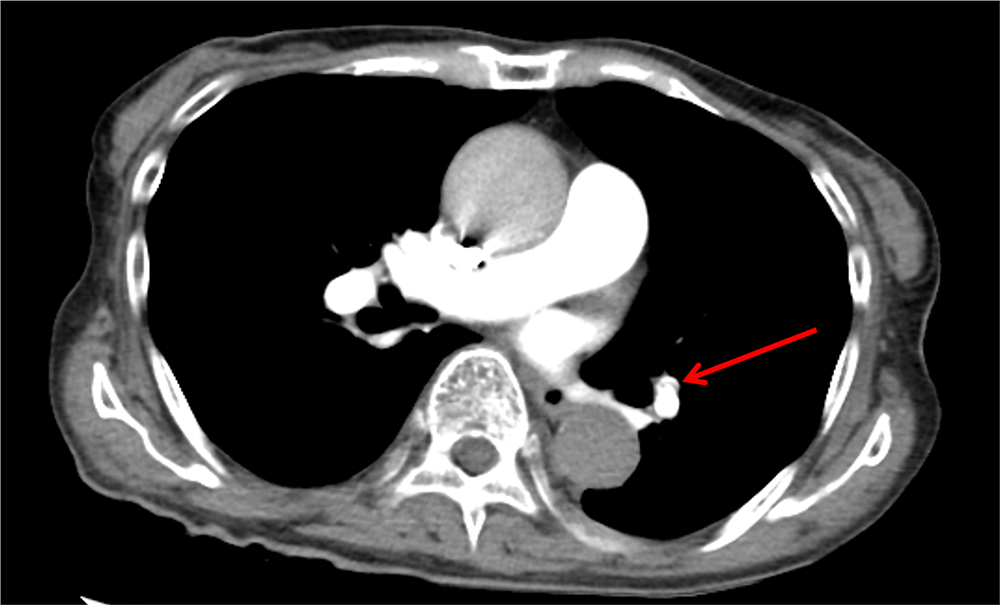

図1.治療開始前の胸部造影CT

肺動脈に血栓による造影欠損がみられる。